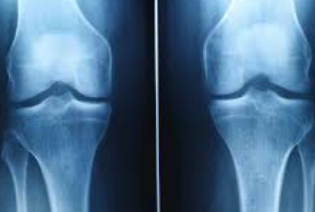

무릎 연골 손상은 현대인에게 매우 흔한 질환으로, 초기 증상을 놓치면 심각한 관절염으로 발전할 수 있습니다. 본 가이드에서는 무릎 연골 손상의 다양한 증상과 단계별 특징을 상세히 알아보겠습니다.

무릎 연골 손상의 가장 대표적인 증상은 무릎 관절 부위의 통증입니다. 초기에는 운동 후나 장시간 활동 후에만 나타나지만, 손상이 진행되면서 일상적인 움직임에서도 통증이 발생합니다. 특히 계단을 오르내리거나 쪼그려 앉는 동작에서 통증이 심화되는 특징을 보입니다.

연골 손상으로 인한 통증은 날카로운 찌르는 듯한 통증보다는 둔하고 깊은 곳에서 느껴지는 통증의 양상을 보입니다. 무릎을 직접 눌렀을 때 압통이 느껴지며, 특히 무릎뼈 주변과 관절선 부위에서 압통이 두드러집니다.